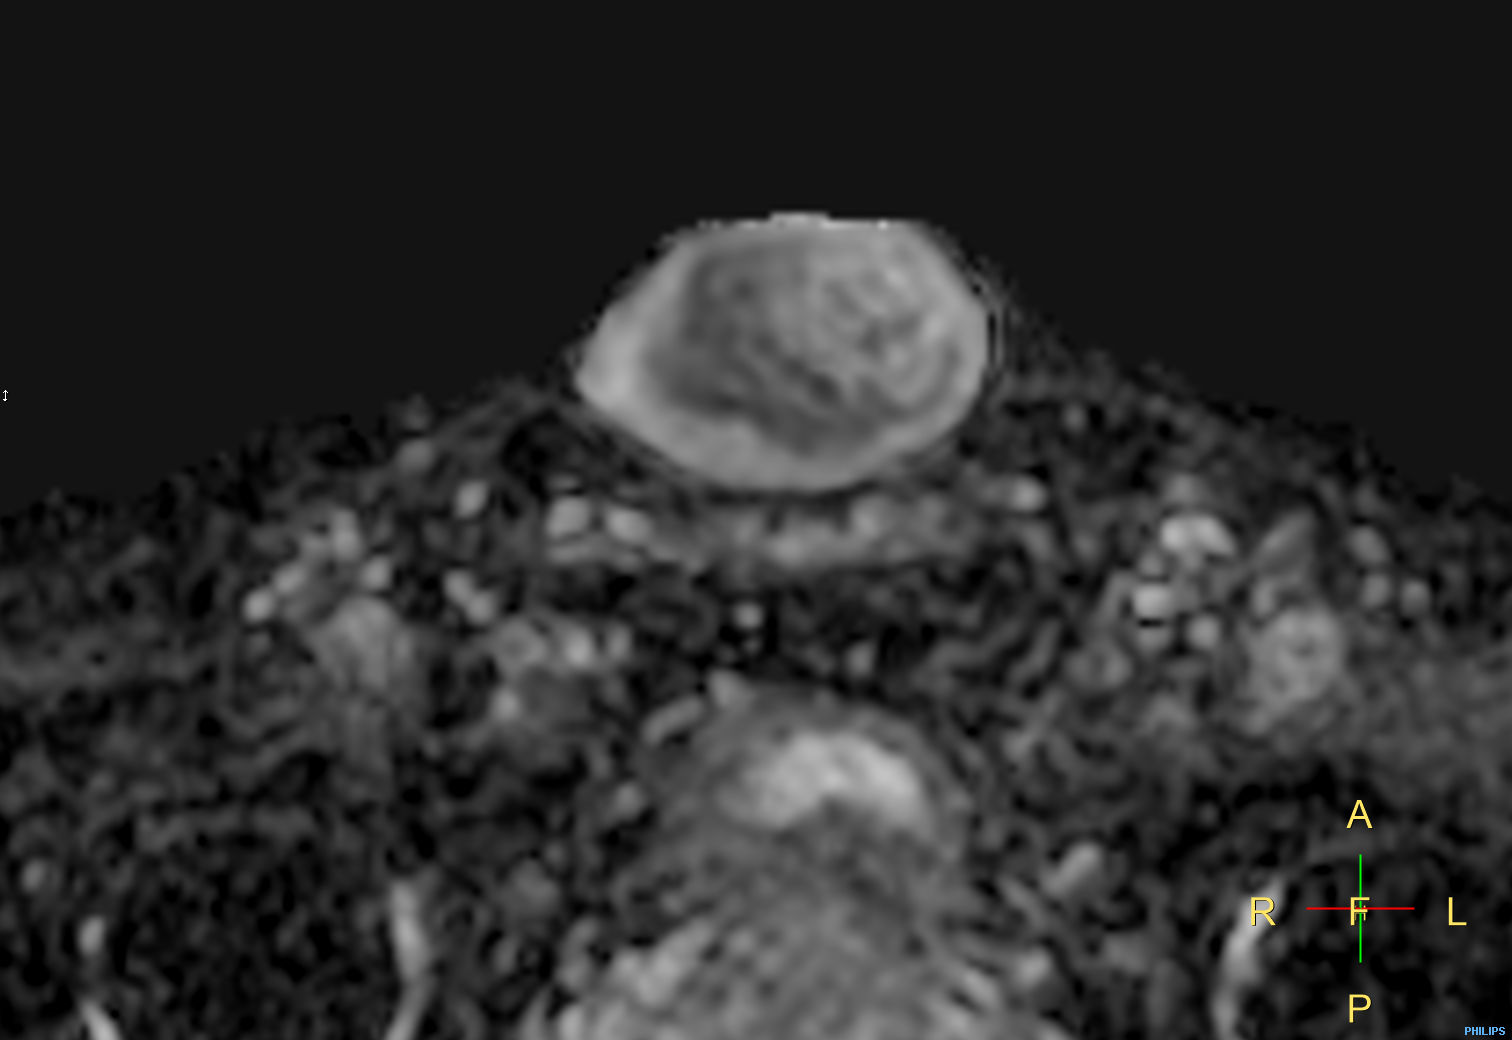

Penile carcinoma

Patient with a penile carcinoma. ExamCard includes Compressed SENSE to shorten exam time, diffusion to achieve high contrast between background and lesions, and MultiVane XD for motion-free imaging in short scan time.

Diffusion (b1000)